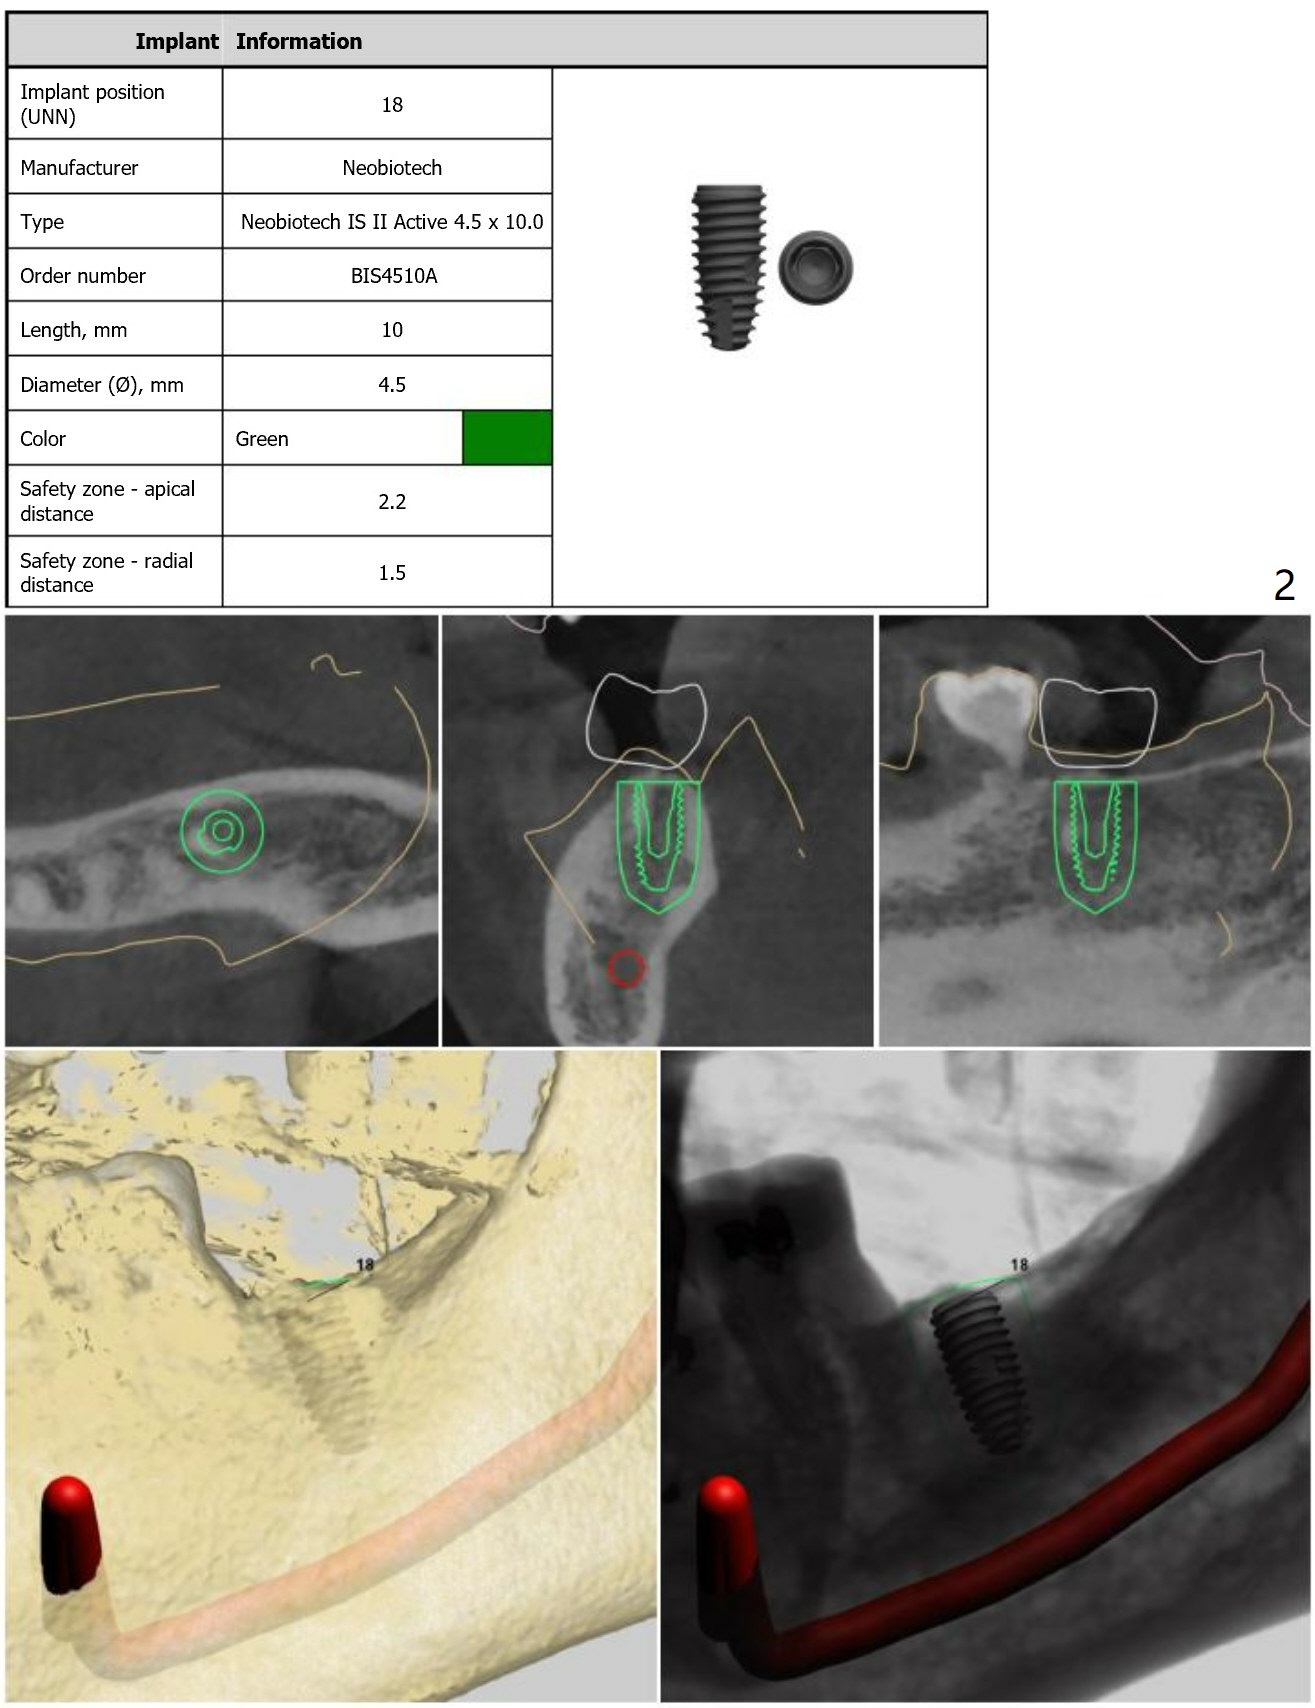

Dense Bone or Residual Root

There is a piece of radiopaque material in the mesial aspect at the site of #18 (Fig.3,4 arrow). After osteotomy and before implant placement, remove the guide to check whether it is dense bone or residual root. Prepare root tip picks. Encourage good oral hygiene (water pik) and postop antibiotic, since he is a diabetic.